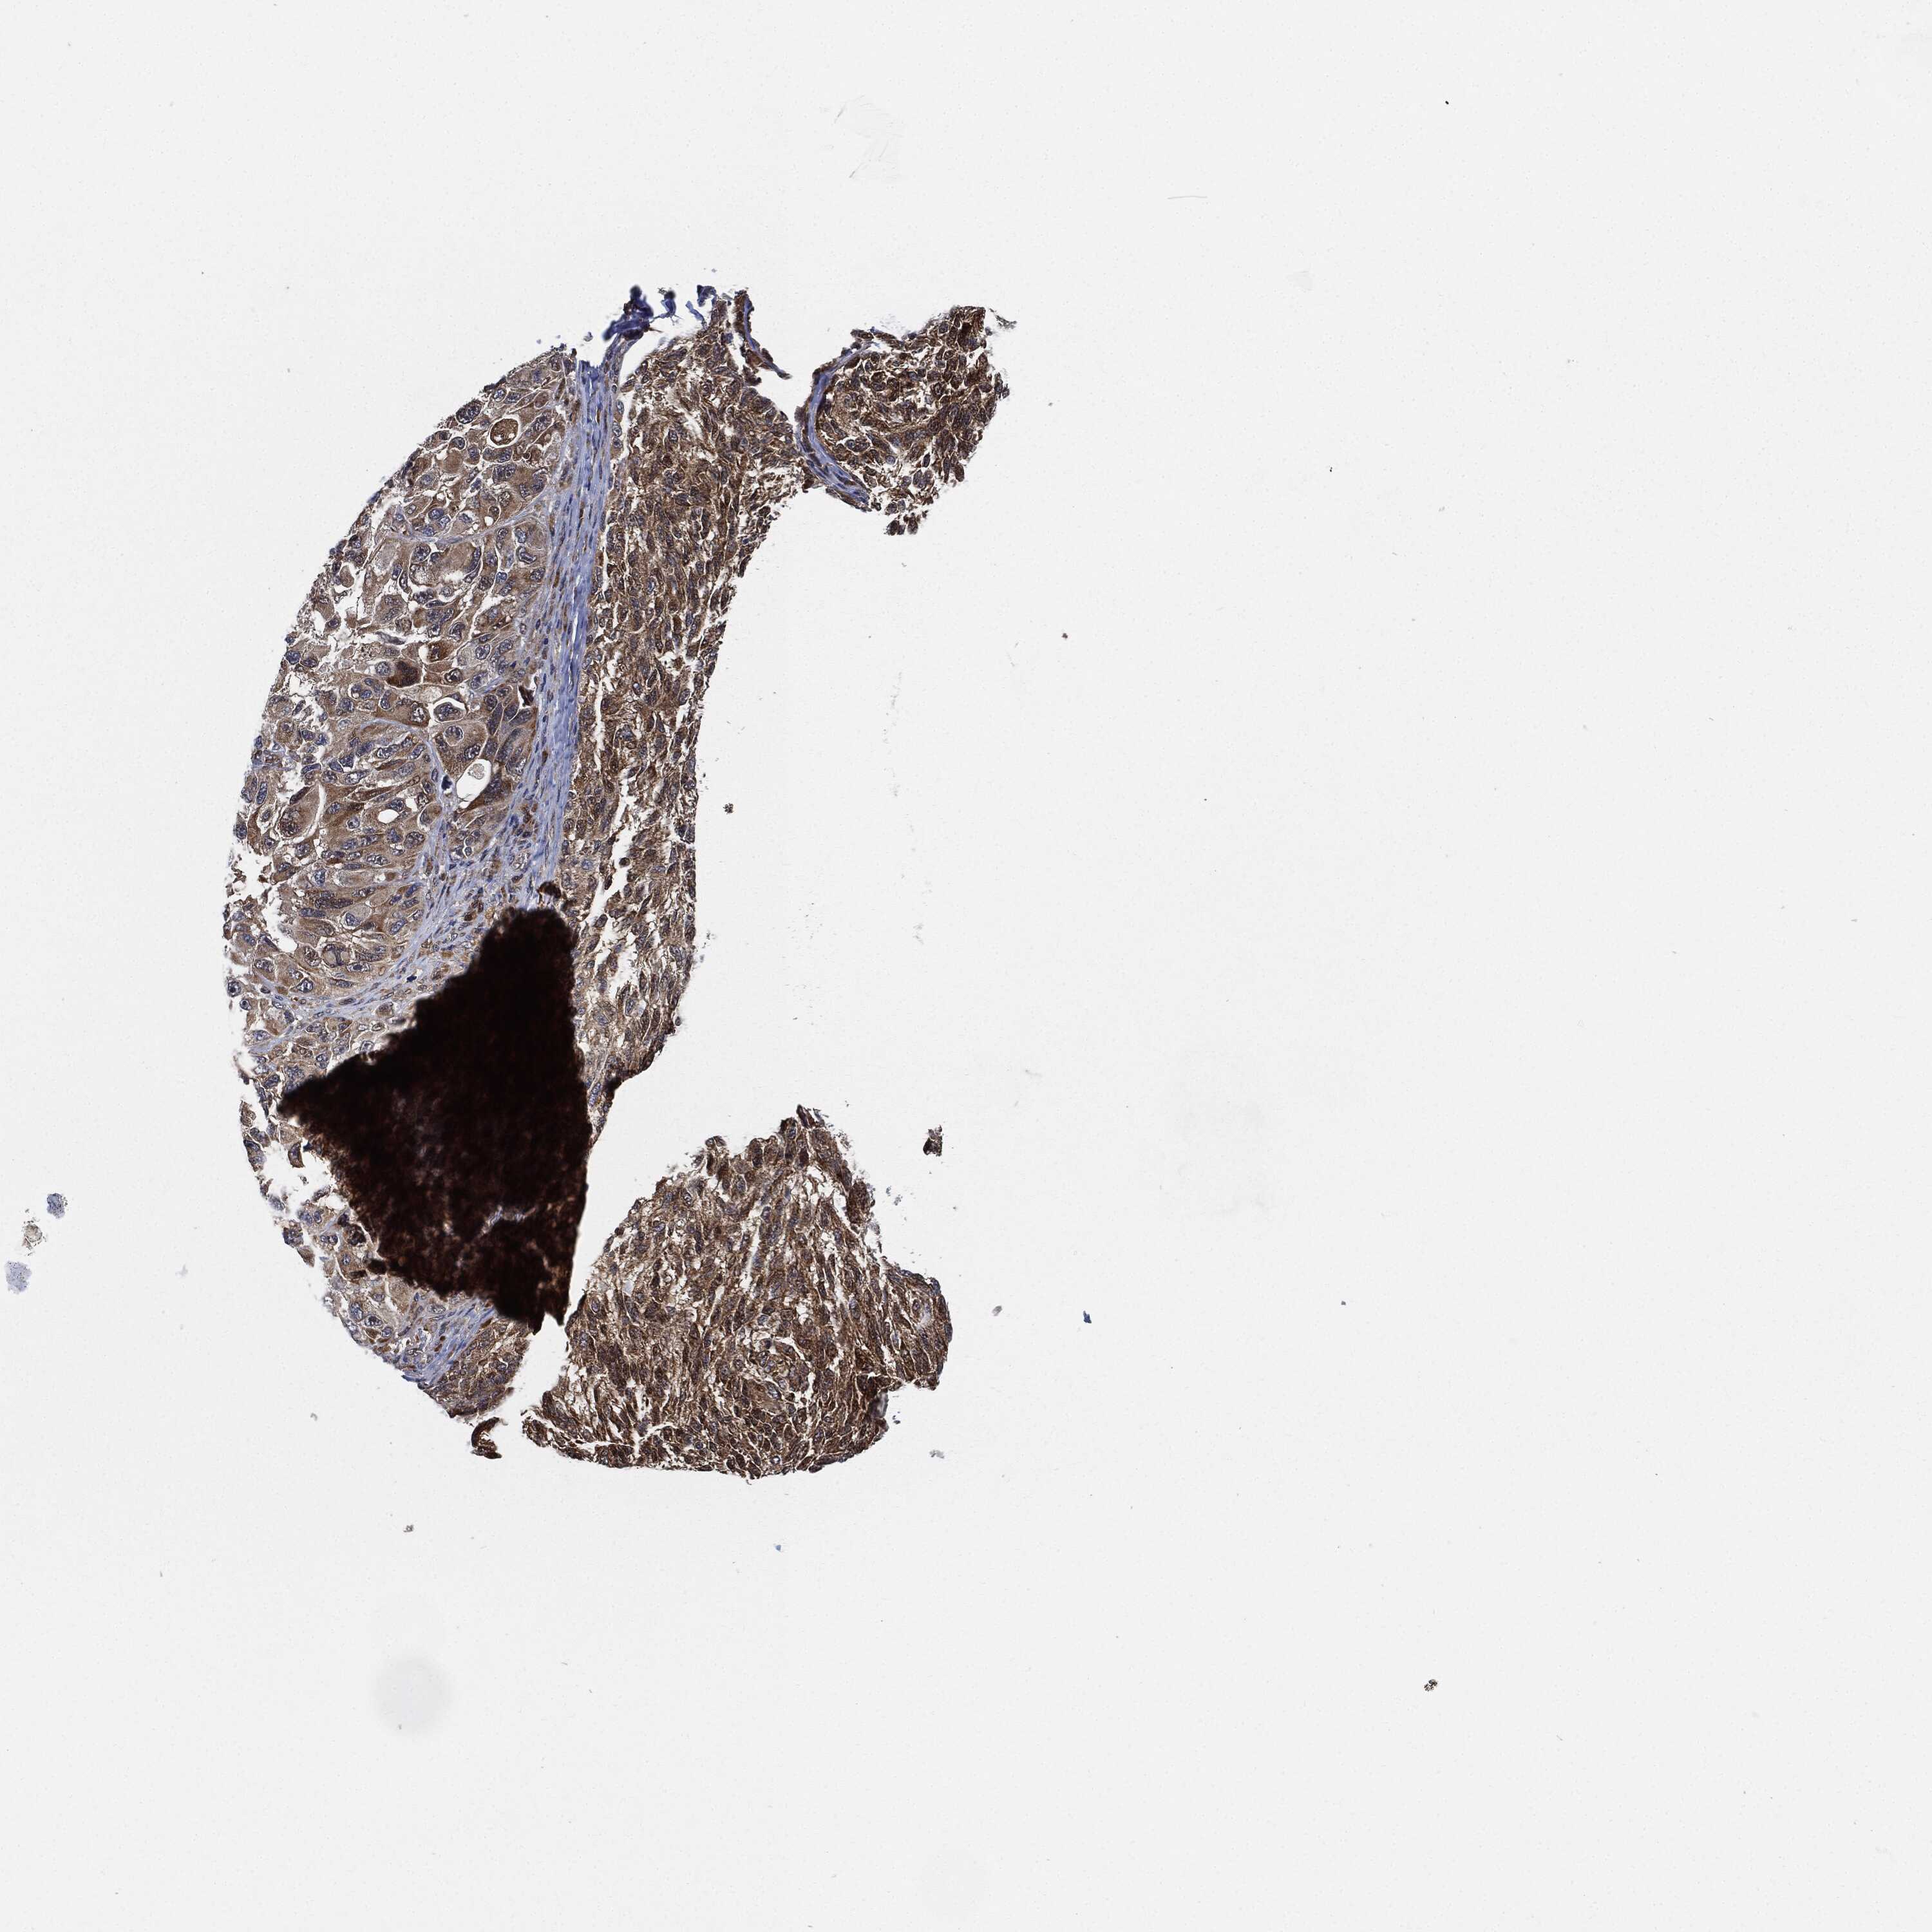

MELANOMA - Protein expressioni

A mouse-over function shows sample information and annotation data. Click on an image to view it in a full screen mode. Samples can be filtered based on level of antibody staining by selecting one or several of the following categories: high, medium, low and not detected. The assay and annotation is described here.

Note that samples used for immunohistochemistry by the Human Protein Atlas do not correspond to samples in the TCGA dataset.

Antibody stainingi

Antibody staining in the annotated cell types in the current human tissue is reported as not detected, low, medium, or high, based on conventional immunohistochemistry profiling in selected tissues. This score is based on the combination of the staining intensity and fraction of stained cells.

Each image is clickable and will lead to virtual microscopy that enables deeper exploration of all samples and also displays staining intensity scores, fraction scores and subcellular localization as well as patient and tissue information for each sample.

Antibody HPA002633

Antibody HPA046758

Antibody CAB010906

Staining

High

Medium

Low

Not detected

Intensity

Strong

Moderate

Weak

Negative

Quantity

>75%

75%-25%

<25%

None

Location

Nuclear

Cytoplasmic/membranous

Cytoplasmic/membranous,nuclear

Malignant melanoma, NOS

Malignant melanoma, Metastatic site

Malignant melanoma in situ